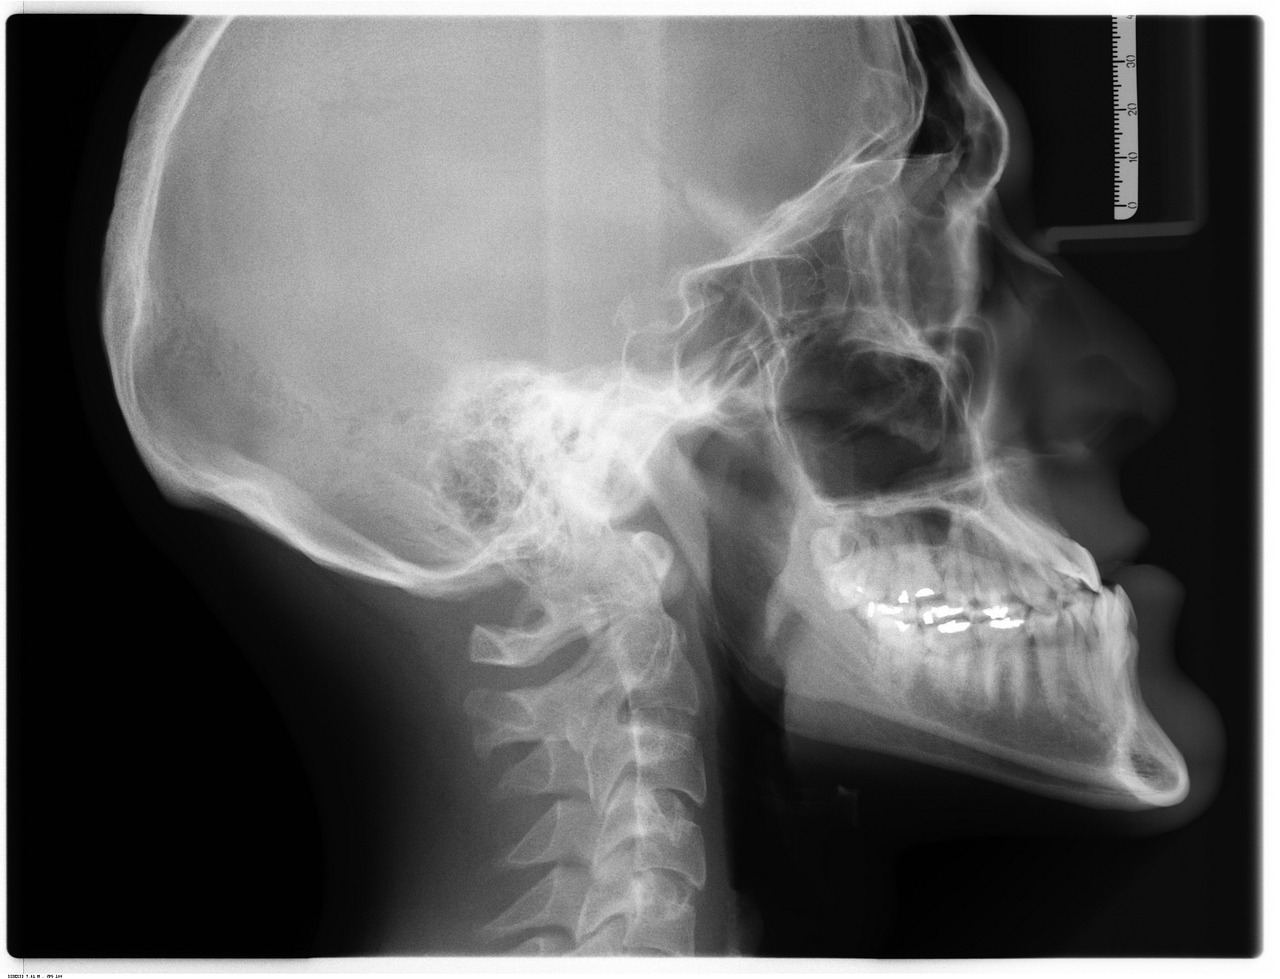

후종인대 골화증이란?

후종인대가 뼈처럼 단단하게 굳어지며(골화) 두꺼워지는 변화를 일으켜 척추관을 지나는 신경을 누르게 됩니다.

이렇게 신경 장애(척추신경근증 혹은 척수증)가 나타나는 질환입니다

목이 좀 아파서 엑스레이를 찍으러 왔다가 알게 되는 경우가 많습니다.

엑스레이 결과에 뼈에 석회가 끼어 있다는 진단을 받는 환자들이 많습니다.

자기공명영상(MRI), 컴퓨터단층촬영(CT) 등으로 신경이 눌렸는지 등을 알 수 있습니다.